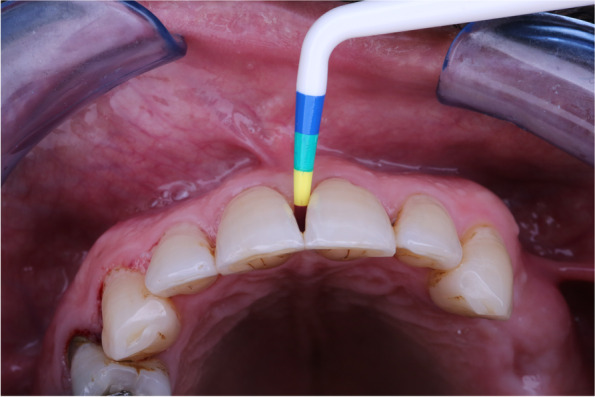

Fig. 3.

Gap sizing for bioclear matrix group

Gap sizing

The black triangle Gauge was inserted under the contact into the black triangle space from facial to lingual until the gauge binds the incisal edges. These were a good reference to look from the occlusal for matrix color selection, in some cases, the gauge was in between colors in these cases using the smaller matrix in curvature (Fig. 3). After deciding if the tooth is small or large, the appropriate matrix in this size was selected.